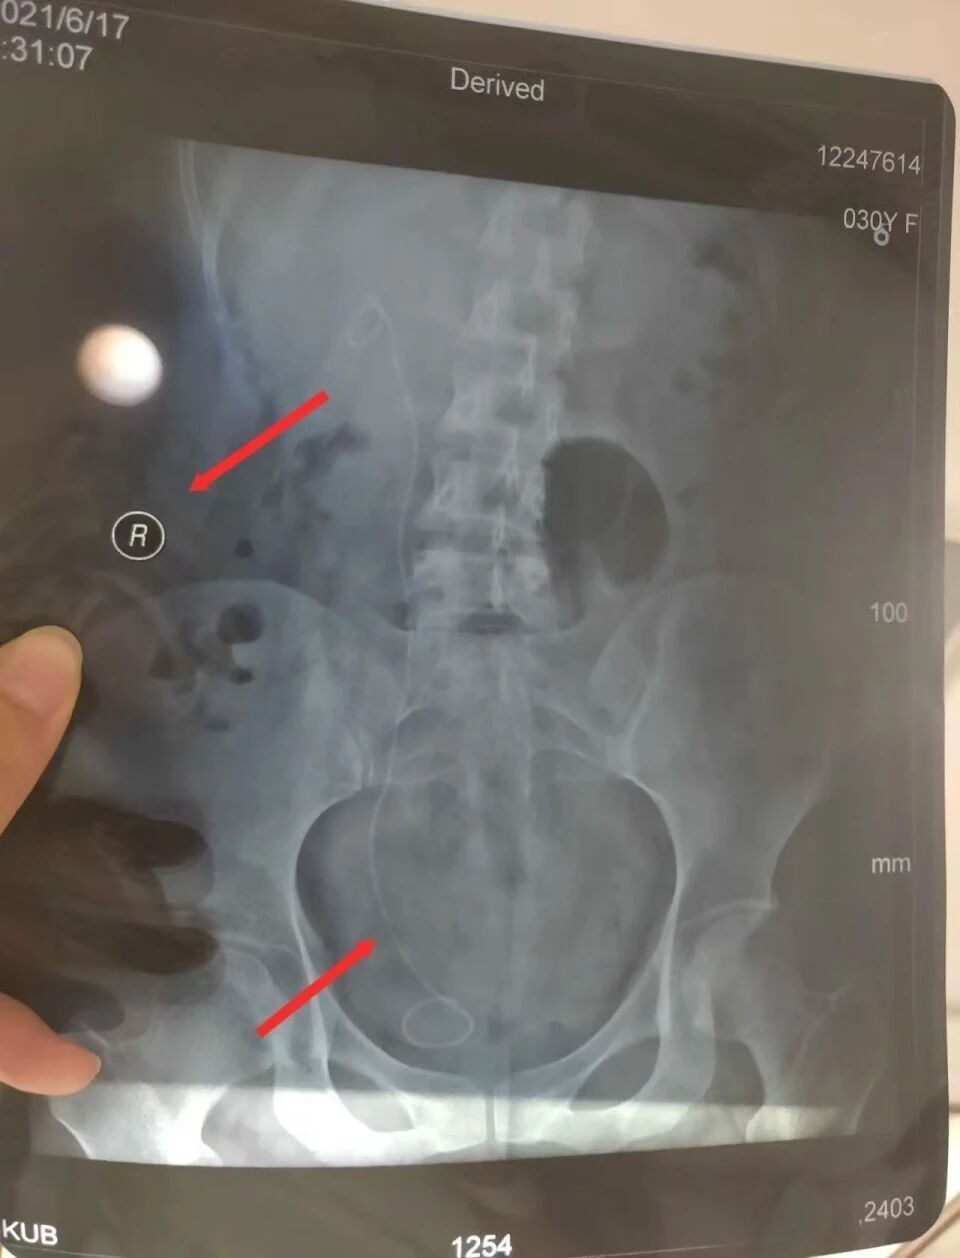

“医生为我确定了左输尿管手术方案,包括术前谈话以及手术知情同意书上,主刀医生也都是这位医生。2021年4月21日下午手术顺利进行,不久后出院。”朱女士说,直到术后两个月,她到医院复查拍CT后才发现,自己原本健康的右输尿管内被施行了手术,患病的左输尿管反而没有手术。

朱女士提供的手术知情同意书显示,病情诊断为左侧肾盂积水伴输尿管狭窄等,拟定手术为左侧输尿管镜检备扩张/内切开。而在手术记录中,诊断仍为左侧肾盂积水伴输尿管狭窄等,但手术名称却成了右侧输尿管扩张术,右侧输尿管镜检查术。

鉴定报告认定,华山医院虽然诊断正确,但手术方案有误,存在告知缺陷。2021年4月19日,医方手术知情同意书拟定手术为“左侧输尿管镜狭窄伴左肾积水”,4月21日,术中医方自行变更手术方案且依据不足(患者既往各项检查如超声、CTU、MR均提示泌尿系病变在左侧,术后超声检查亦显示病变在左侧),术中未向患方进行告知并取得患方知情同意,术后亦未告知患方该情况,患方至6月17日门诊复查时知晓该情况。医方告知存在缺陷,在一定程度上延误了患者左侧输尿管病变第二次治疗,时间约2个月。